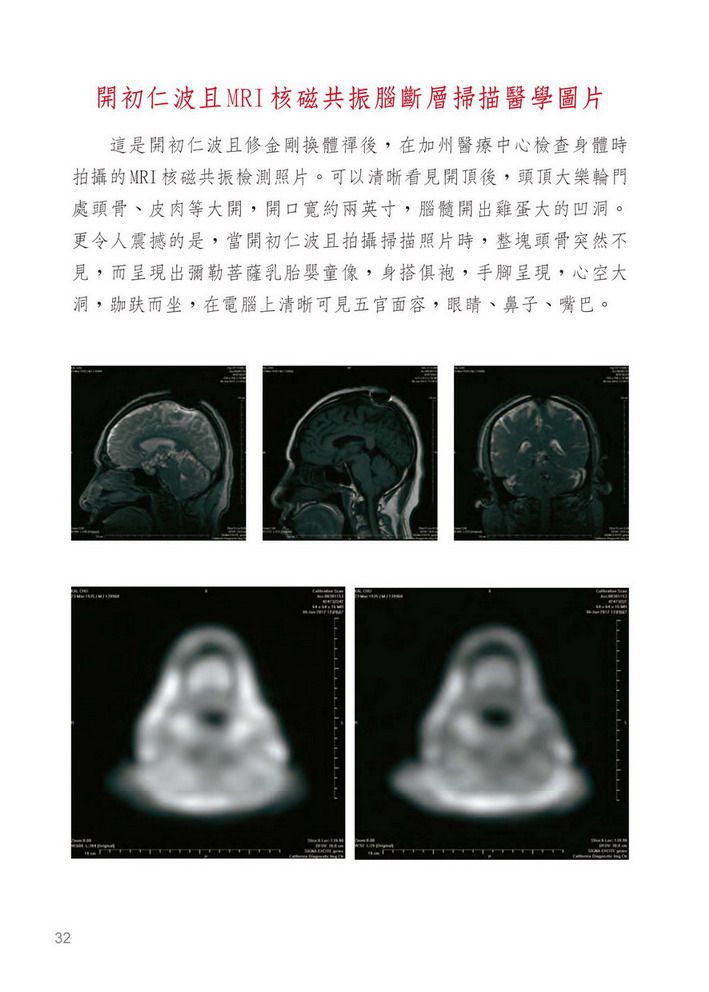

今天既然說到開頂的事也明告世上修行之人,你千萬不要相信插上吉祥草這就是證聖的境界啦,真正證聖不是凡夫的事,首先看一下那自吹開頂的人他真的開頂了嗎?有證據嗎?這可不是插上一支吉祥草或用脫髮水脫掉一縷頭髮就證明開了頂的,你們要弄清楚,那吉祥草硬如竹籤,哪一個人的頭皮都能隨處插上。哪怕吃下幾粒具生命力能在弟子自己手中活躍的金剛丸,這頂也開不了的,那一定要服上一口真正的佛降甘露作為法緣基礎,而且要灌金剛換體禪的境行之頂才能打開大樂頂門,這非同小可,正如妙空法師體悟說:「驚天動地啊!」真正開頂可不這麼簡單啊!學佛人要知道,但凡學佛成就或往升者必須要開了頂才行,而且任何佛法只要修成就,就會開頂,但都是中陰身成就的,如果頂都沒有開,神識又從什麼地方出沒肉體呢?只能由六道轉輪處出走神識,其實不具《解脫大手印》灌頂境行的人是不行的,就是破阿法開了頂,最多也只有一毫米寬,而且神識一當出體後就回不去了,所以只能中陰往升淨土,亦稱為中陰身最好的救度法。只要是受了《解脫大手印》勝義內密灌頂境行法,其功德力大於常規佛法萬倍之多,神識出體後又能返回,十分自由,這功力之強大,不是一句空話,而是實語、如語、無妄語。比如能讓受灌者在一個時辰之內證到虹身境界,但是修大圓滿需經十二年之久,乃達成就者少之;又如金剛換體禪,也是只需一個時辰開大樂輪門之頂,用以現代科學檢視證實頭頂開一指到二指寬的空口不等,乃至其洞深入腦底,達透五輪,神識出入自由,這在常規佛法是沒有的功德道力。要注意的是已經修《解脫大手印》的人,你除了只能加修護法之外,其他任何佛法皆不可以混入修持;但是凡沒有領受到境行修持的人,可以只修《解脫大手印》前行和正行,也可以不修「福壽財富成就法」而加入你曾經修過的本尊正行,溶入在《解脫大手印》前行、正行中修持。但切記不可以與你原有的前行混修,如果你認為法本太長,你可只選《解脫大手印》前行、正行加入你原有的本尊心咒和形相觀修就很圓滿了,只要是加入《解脫大手印》前行、正行、結行而修,就這麼簡單的修持,其功德力也是比常規佛法的成就要大十幾倍的。比如開頂成就解脫就是鐵證,我看到開初仁波且和妙空法師是真開了頂的,而不是那虛名的所謂開頂插吉祥草,他們是跟我一樣受《解脫大手印》金剛換體禪境行灌頂開的頂。在灌頂當時,頭頂肉與骨的表顯則是完好無異樣變化,卻能開能關,在醫學的照片檢視上清清楚楚就是開頂了,並且照到了靈識出體的剎那氣相體,確實證明肉與骨頭、腦膜、腦髓都不見了一到二指寬,其中一位出現螺旋狀洞口,一條線一直深入大腦中心,另一位則洞有雞蛋大小,直入腦底,他們二位才是真金大聖德、大王臣啊!無論什麼人所講空洞的理論都是代表不了實際成果的,所以千萬不要迷信那些說假話空洞理論派的假聖德。有的人借用他的上師是名門正聖的旗號,稱自己是正宗法承人,但是要清楚往往一位大德往升了以後,他門下的弟子們都會爭相爭奪繼承他的法脈,就算你真正把他的法脈完全繼承了,你所修的那些佛法跟《解脫大手印》比起來也是天地之差啊!比如有兩個小時成虹身的法嗎?有一個時辰金剛換體禪開頂二指寬,神識出沒自如嗎?根本就找不到,所以我說天地之差。